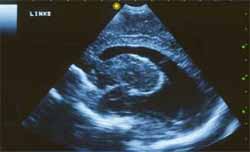

Es por eso que en algunos países se realiza tratamiento antibiótico durante el primer año de vida, aunque su beneficio real aún no ha sido definitivamente demostrado. La infección del feto puede producir un aborto, tener una variedad sub-clínica con síntomas tardíos o permanecer asintomático, o presentar la triada de corio-retinitis, hidrocefalia y calcificaciones cerebrales. Otras lesiones que pueden asociarse a la toxoplasmosis congénita son microcefalia, convulsiones, órgano megalia, rash y fiebre (Ver ecografías).